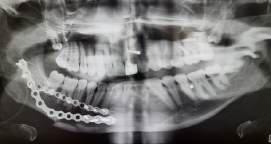

Dessa veckor fick vi se och göra som mest Allt ifrån att assistera under flera ortognatoperationer, frakturer och borttagning av cystor till att själva få extrahera en massa tänder. Denna kurs uppskattade vi båda som allra mest!

Nicki fick assistera under operation där det hade skett en fraktur på höger sida av mandibeln